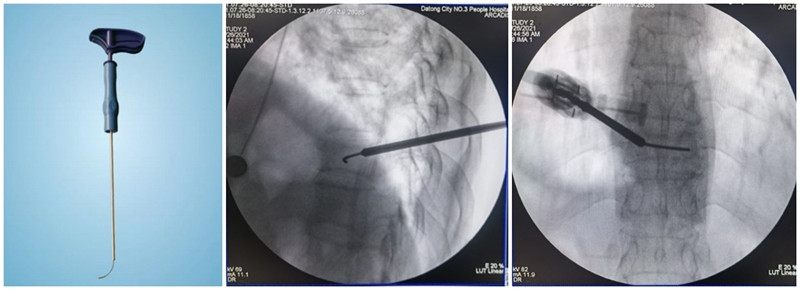

(2)弯角导丝开腔:弯角骨钻开腔器械刺入椎体时,注意开腔工具手柄与伤椎终板平行,不要强行开腔,多透视侧位,否则弯导丝可能穿破终板,导致医源性骨水泥渗漏。C形臂X线机正位透视下,导丝到达椎体对侧椎弓根处即可。